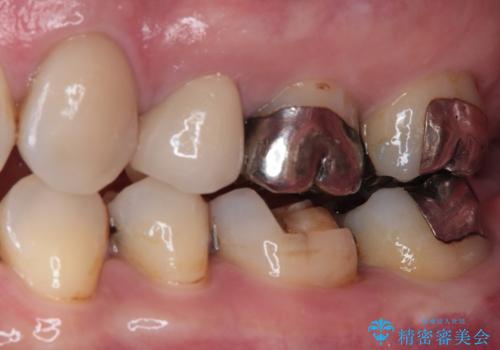

拡大鏡視野下にて、メタルインレーの範囲が大きく虫歯もあったため、オールセラミッククラウンにて修復を行いました。

見た目、噛み合わせともに満足していただけました。